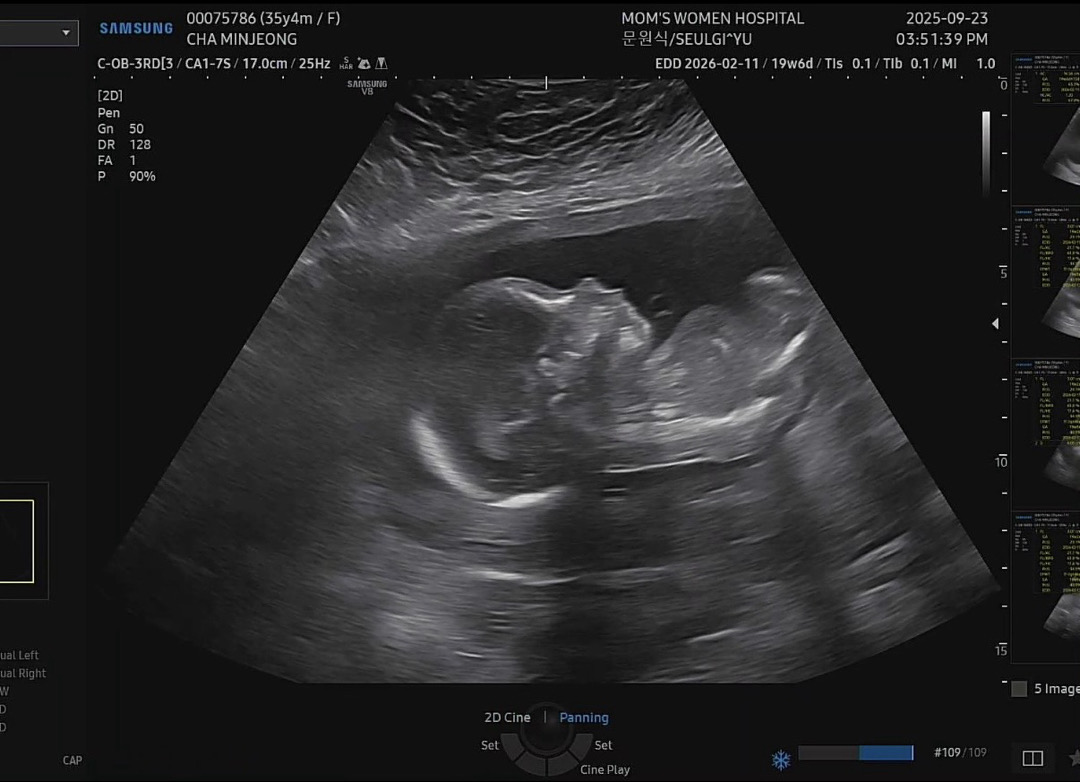

20주촘파

촘파상으로도 벌써 잘생긴거같은,.. ㅋㅋㅋㅋ 도치맘인가요 ㅋㅋㅋㅋ